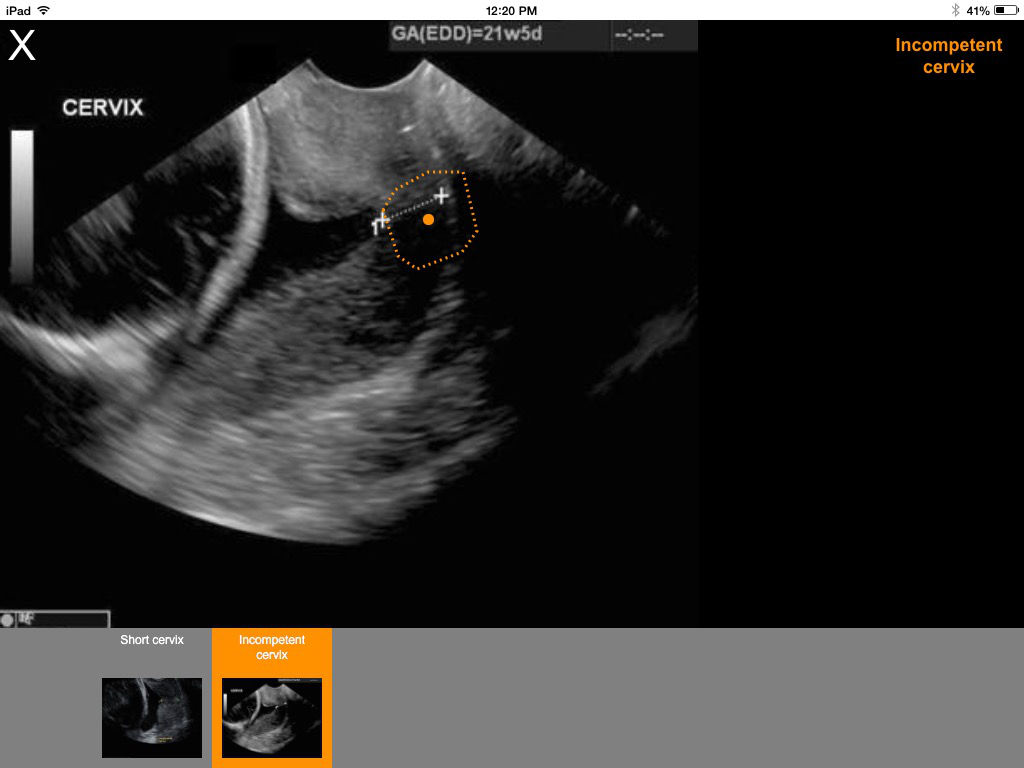

obNAV is a fast and easy way to learn ob/gyn and breast ultrasound. Using proven learning methods, iPad-based obNAV accelerates learning by using modeling, worked problems and germaine level teaching. This system is an intuitive, easy-to-use, comprehensive reference guide—like a teacher at your side—that you can access anytime, anywhere … even while scanning, for just-in-time-near-action learning. Works offline. Frequent updates. Features include: Learning modules: general gyn, 1st trimester, 2nd/3rd trimester, and breast ultrasound Labeled ultrasound video clips with highlights Step-by-step protocols Labeled pathology libraries Expert tips and references Ultrasound physics, knobology, techniques Probe placement and measurement guides Labeled 3D anatomy MRI scans Self-Test questions … and more